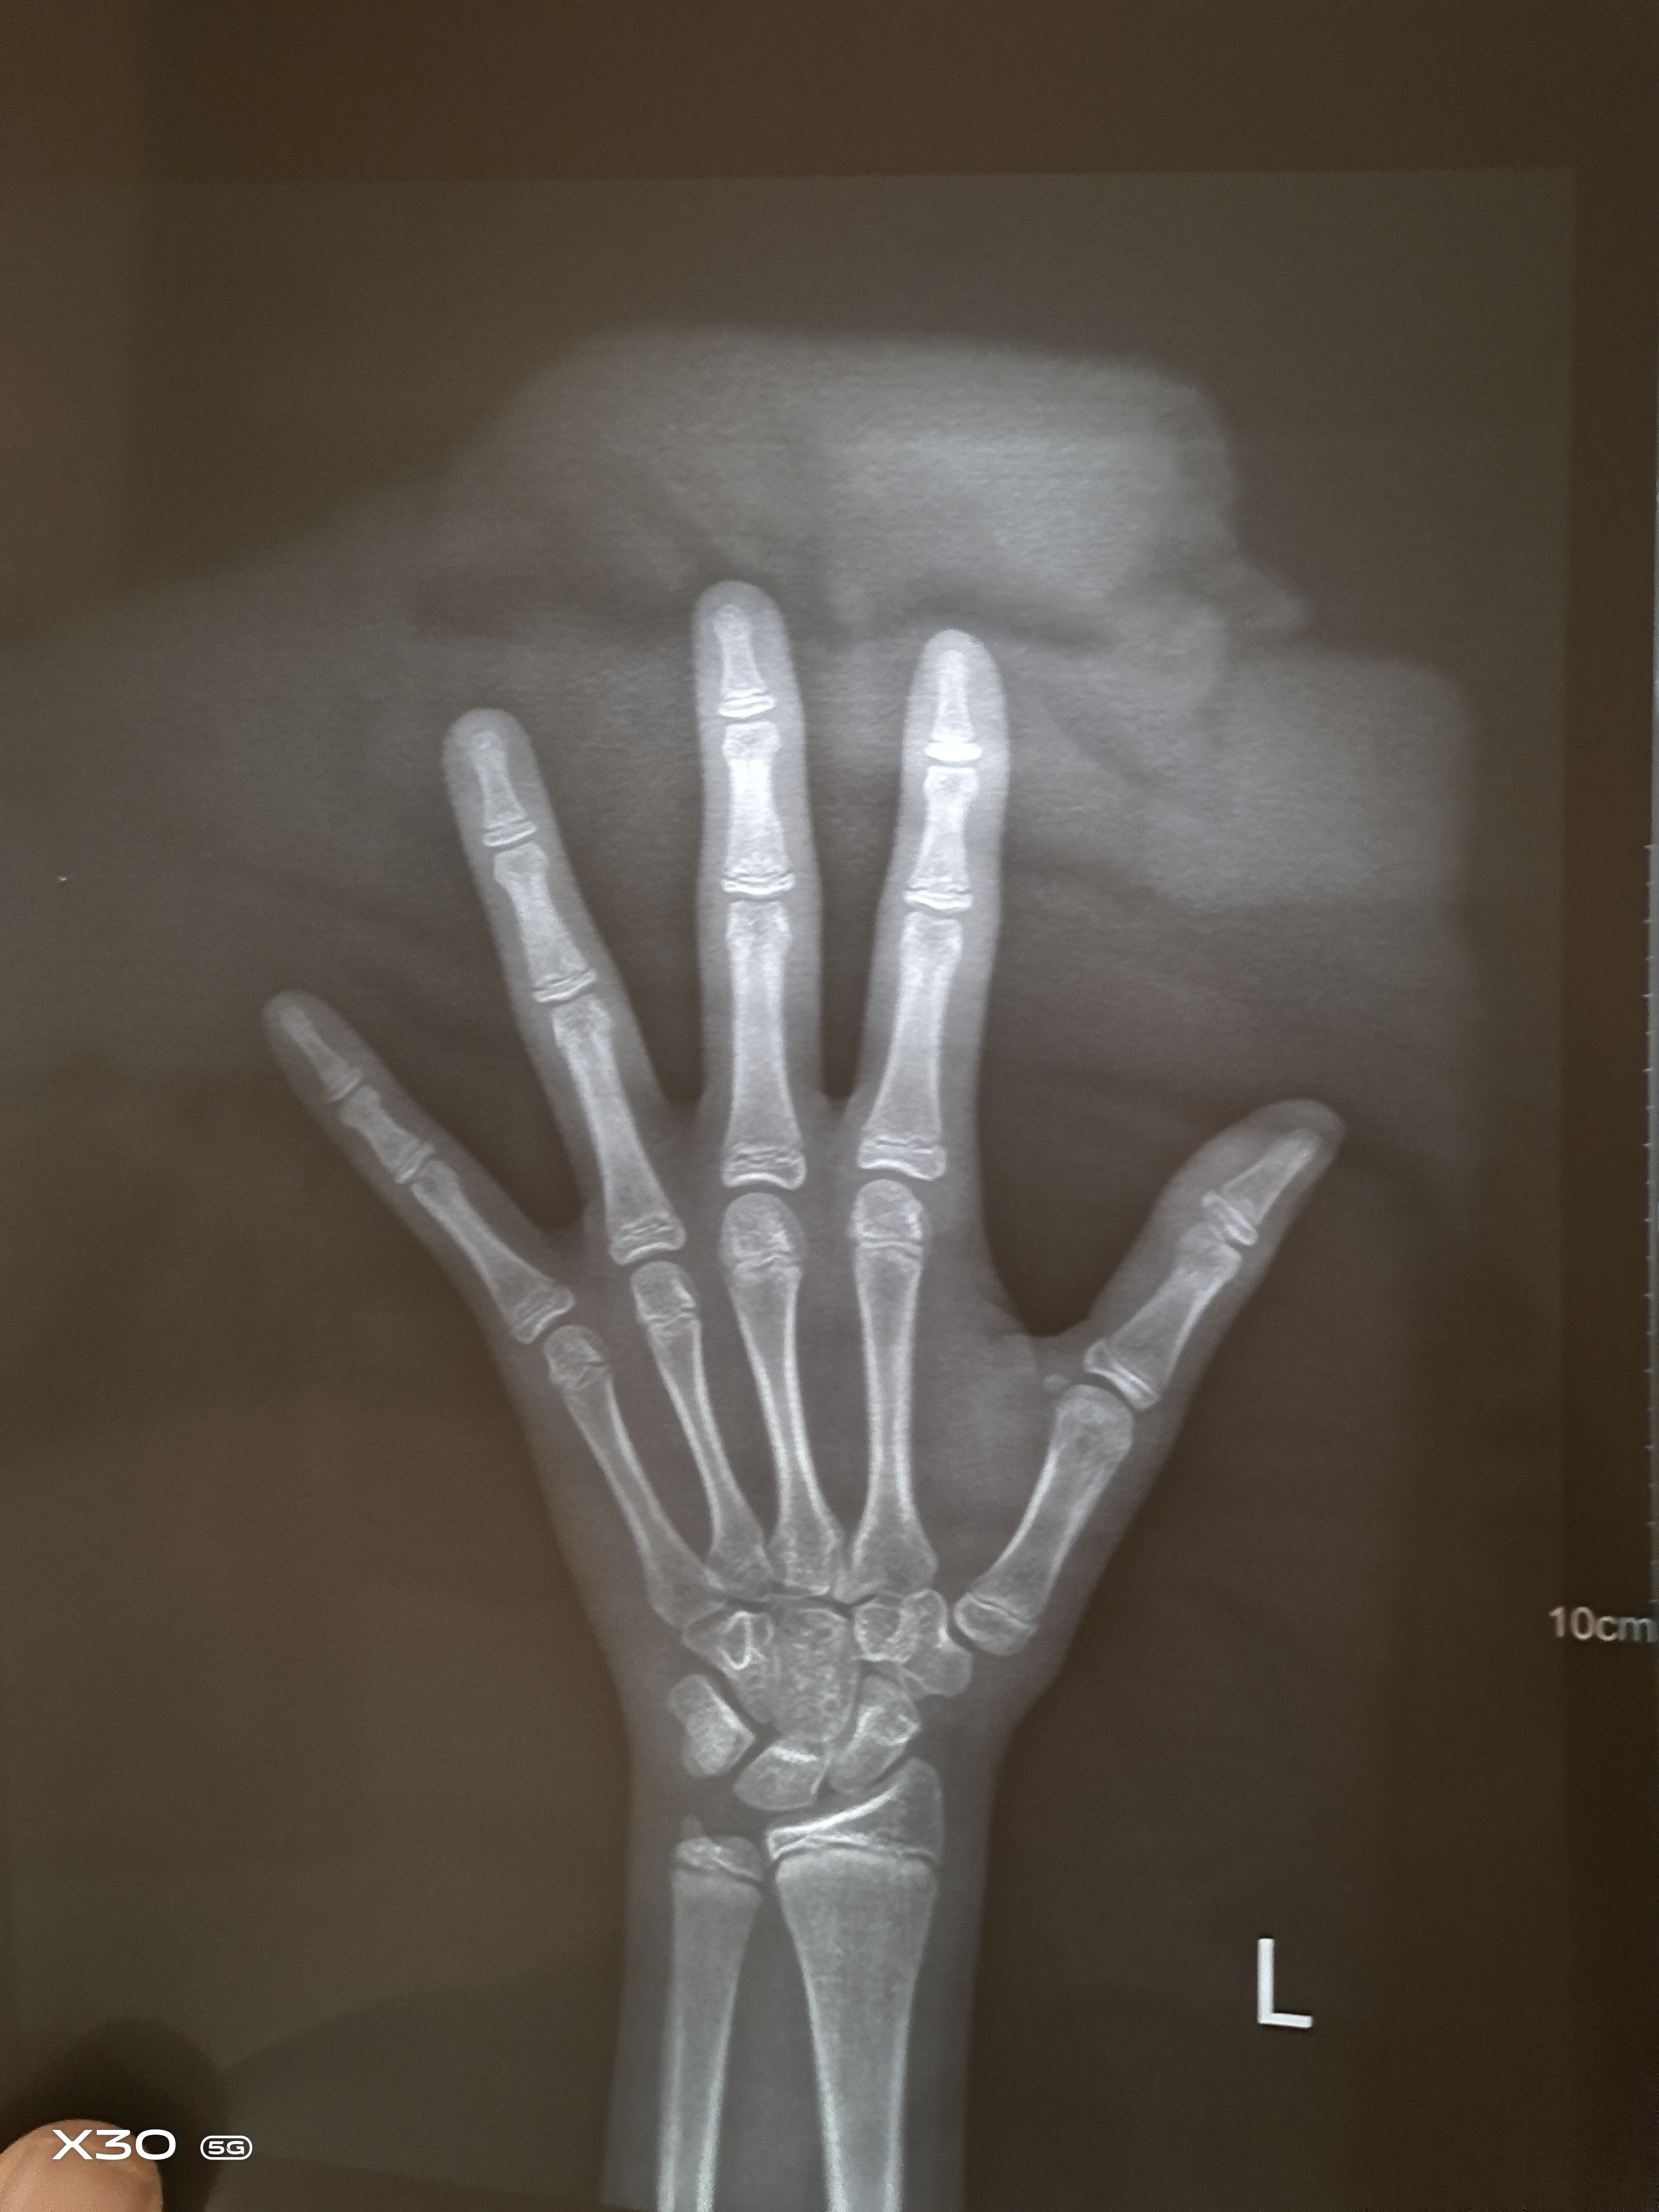

还有一点需要注意的是,评估孩子的身高状况,需要看骨龄,而不是单纯地看生理年龄。

比如说我在门诊中遇到的一个男孩,今年10岁,身高141厘米,根据这个曲线图来看的话,孩子身高在中间线上,处于平均水平;可是结合孩子骨龄片来看,孩子骨龄偏大两岁,已经有12岁了,根据12岁来画点,孩子的身高接近最后一条线,已经接近矮小症了。

4. 定期监测骨龄

可以把拍骨龄片,加入日常体检的项目中、定期监测。骨龄片是评估孩子生长情况、生长水平最便捷的方式。能拍X光的医院,都可以拍骨龄片。